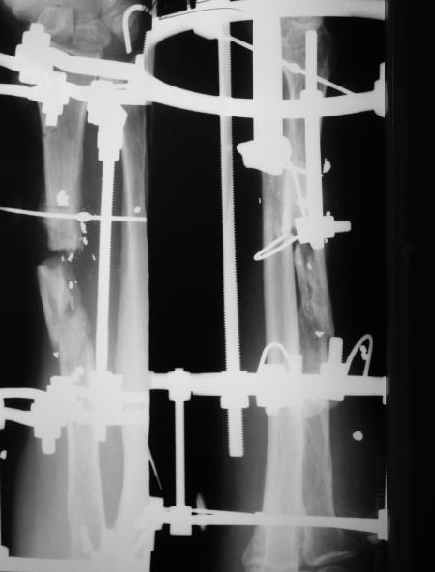

Мужчина 36 лет 5 мес. назад получил дробовое ранение правого предплечья с переломом лучевой кости, повреждением лучевой артерии и срединного нерва.

В больнице по месту жительства обрабатывали рану,сделали несвободную кожную пластику, синтезировали спицей интрамедуллярно, потом убрали. Свищей нет. Линейный рубец по лучевой стороне, приживший лоскут по ладонной (см. картинку).Cращение не произошло (см. снимок).Нейрохирурги что-то надеются сделать, но условием ставят стабилизацию лучевой кости.Какой вариант тут предпочесть? Представляется оптимальным аппаратом дозированно подправить длину и ось, и закрыто ввести интрамедуллярный стержень. Не особо даже рассчитывая на сращение, а только восстановить форму и длину кости, и создать "эндопротез диафиза". Или подумать про какие-то другие варианты?A male 36 years old 5 month ago sustained a gun-shot wound with the radial fracture and lesion of a.radialis and n.medianus. Debridement was performed at the initial hospital, full-thickness skin grafting and intramedullary fixation of the radius by a small wire, which later was removed. No sinuses and signs of infection to date. A linear scar on the radial side and the healed flap (see image). Healing was not reached (see x-rays).Neurosurgeons hope to do something with the peripheral nerves but only in case of stabilization of the radius.Which treatment modality should be preferred? I would perform gradual alignment with the Ilizarov, and perform secondary closed nailing. Even not to expect to reach union, just to restore length andalignment with the "shaft endoprosthesis". Or it is worth to think about other options?

Пока мы наложили аппарат для восстановления оси и длины лучевой кости. Снимок прлагаю.

В приложении - снимок по окончании дистракции, и после смены аппарата на стержень (довольно толстый, 5 мм). С входом в канал на центральном отломке пришлось малость попотеть, промежуточный отломок его прикрывал. Но все-таки удалось закрыто проколупать. Надеюсь, дня через 3-4 после операции можно будет передать пациента нейрохирургам. Буду признателен за критику и комментарии.

Все за и про интрамедуллярной фиксации этого перелома луча уже обсуждались - все идет по плану.

Твоя концепция стабилизации отломков, своего рода *протезирования* лучевой кости продемонстрирована на Ргграммах. Прямого кость-кость контакта между дистальным и промежуточным фрагментами не получилось, что может скомпрометировать сращение перелома, хотя при первично стабильной фиксации и сохраненной надкостнице можно рассчитывать не

формирование периостальной мозоли (видимо этот механизм и работал в твоих прежних случаях).